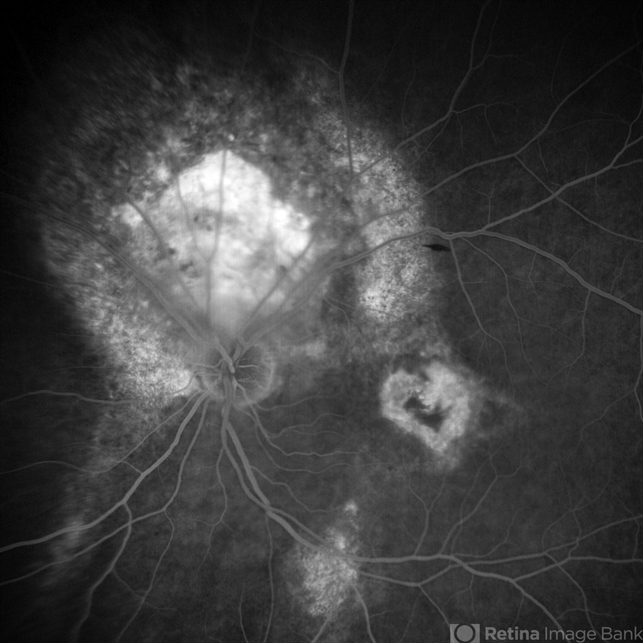

- Fundus examination, Fundus Fluorescein Angiography, Choroidal Hemangioma

- A 53 years male patient presented with decrease in vision in left eye for 6 months. His vison in left eye was counting fingers 1 meter. His vison in right eye was 20/20. Fundus examination in left eye depicted presence of large orange shaped elevated subretinal mass superior to optic disc with scar in macula. We made clinical diagnosis of Choroidal Hemangioma with macular scar. Fundus Fluorescein Angiography (FFA) in left eye revealed early fluorescence in area corresponding to Choroidal Hemangioma which persisted in late phases. Macular scar was “HEART” shaped on FFA which was very unique incident finding.